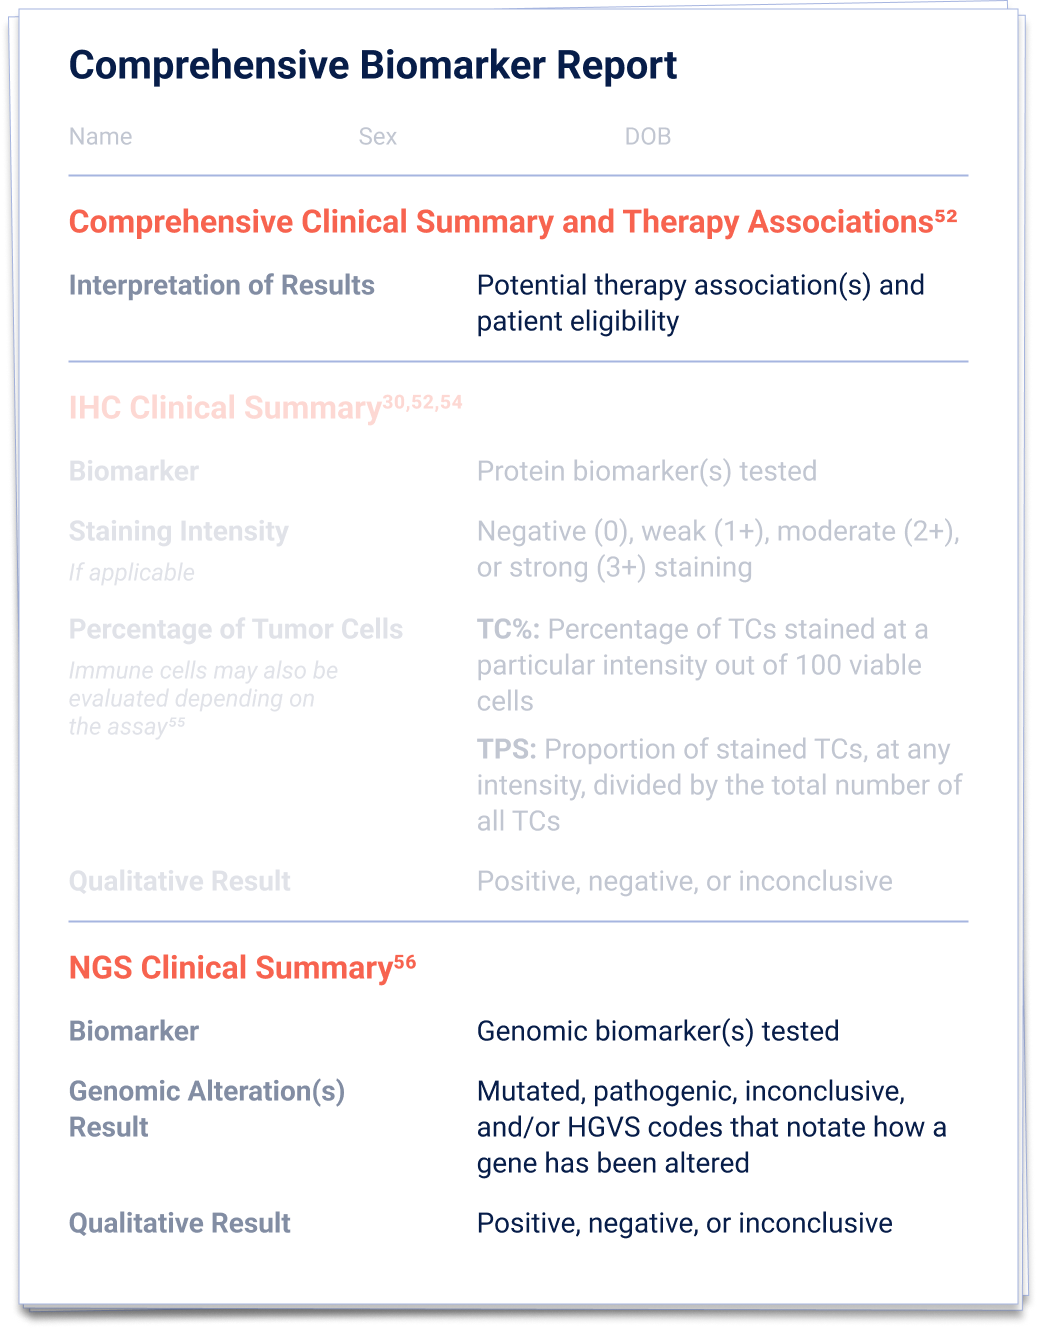

52. Penault-Llorca F, et al.

Virchows Arch. 2022;481(3):351-366.

56. Schmid S, et al.

ESMO Open. 2022;7(5):100570.